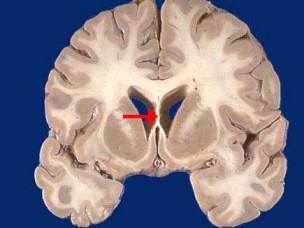

问题 如图箭头所示为大脑哪个部位 ( )

选项 A、第三脑室 B、中脑导水管 C、透明隔 D、屏状核 E、脉络丛 一、单项选择题

答案 C